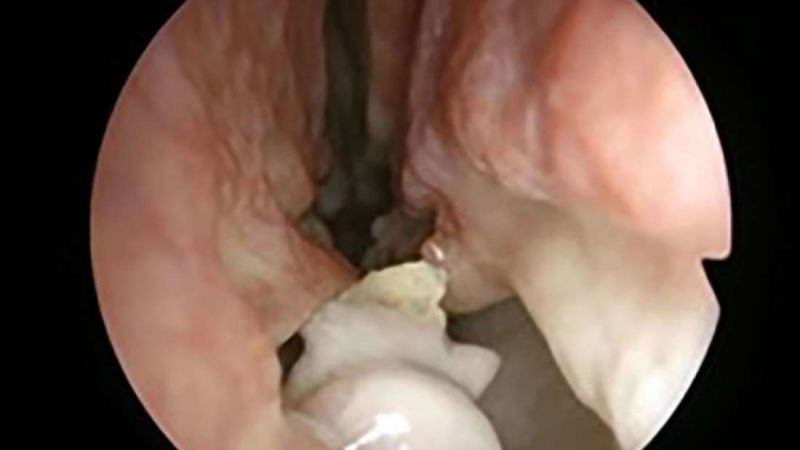

Descubre después de dos años con la nariz taponada que tenía un diente creciendo en la nariz

Un hombre de 59 años acude al Hospital Aarhus en Dinamarca aquejado de un orificio nasal izquierdo bloqueado, una secreción extraña y un sentido del olfato reducido. Los médicos examinan su nariz y el resultado es parte de la literatura médica: un diente adicional le crecía en la nariz.